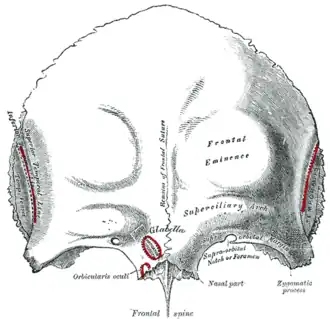

Frontal bone. Outer surface. (Frontal eminence is labeled at center right.) | |

A frontal eminence (or tuber frontale) is either of two rounded elevations on the frontal bone of the skull. They lie about 3 cm above the supraorbital margin on each side of the frontal suture. They are the site of ossification of the frontal bone during embryological development, although may not be the first site.[1]

The frontal eminences vary in size in different individuals, are occasionally asymmetrical, and are especially prominent in young skulls. The surface of the bone above them is smooth, and covered by the epicranial aponeurosis.